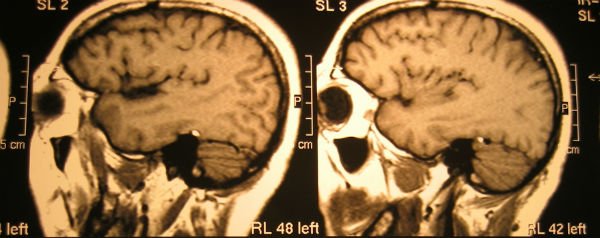

Kathryn E. Demos van Brown Medical School in de Verenigde Staten trok 48 studentes door een hersenscan terwijl ze verschillende plaatjes te zien kregen van eten, dieren, en mensen in seksuele en niet seksuele posities. Demos en haar team maten vervolgens de activiteit in de nucleus accumbens, het deel van de hersenen dat verantwoordelijk is voor beloning en plezier.

Wat bleek? Studentes waarvan de hersenen heftiger reageerden op de seksuele foto’s, hadden naar eigen zeggen een hoger libido. In een halfjaar hadden deze studenten ook daadwerkelijk vaker seks gehad dan de studentes die minder heftig op de pikante plaatjes reageerden.

“Het is nieuw dat we nu voorspellingen kunnen doen over gedrag, op basis van eerder gemeten hersenactiviteit”, zegt Brown tegenover The New York Times, over de studie die is gepubliceerd in het Journal of Neuroscience.